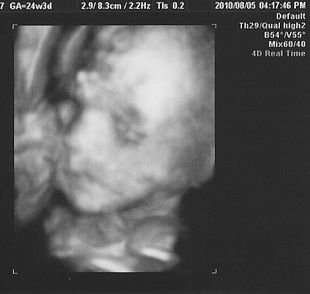

11月11日(木)に出産して、13日(土)から母子同室開始。 今までは、Håkichiの授乳以外は寝るかテレビを見るかだけだったんだけど、同じ部屋にHåkichiがやってきて、Håkichiの観察が勢いを増します(笑) この時に一緒にでる声がまた可愛い♪ なぜか手が異様に白いんですけど・・・・・マミーとダディがほどよくミックスされてるならいいんだけど、パーツごとに違うのは怖いのでやめてください(汗) そして予定日より2週間ほど早くこの世界に出てきたHåkichi。本人はまだ私のお腹の中にいると思っているのか、自然に壁の方に移動していって側面にタッチ。 Håkichi、何度ベッドの中央に戻しても、側面目指して移動し、手と足だけにとどまらず、顔までくっつけてました。 HåkichiはJ君によって非常にコンパクトにまとめられました。 さてここから、新米マミー&ダディにより子育てが始まるわけなんですが、退院した当日は家に帰って何をしていいか分からず、とりあえず2人で観察。 そして翌日。おむつ交換、授乳以外のほかに新たな試練が!! そう、沐浴です。沐浴指導は退院前日に1回やったのみで、まるで自信なし。しかも私たちが実践しようとしている沐浴は普通の沐浴とは違うし・・・ ベビーバスを購入するに当たって、一般的なものは1ヶ月くらいで使わなくなってしまうというのを聞いていたので、私たちが選んだのは ↓ ↓ ↓ ↓ Tummy Tub (←公式ウェブサイト) 「ママのお腹にいた時と同じ、赤ちゃんがいちばん落ち着ける姿勢で沐浴できる」というコンセプトが気に入り、プラス私とJ君が普段からシャワー浴しかしないので、Håkichiをお風呂気分にさせてあげるのはこれが一番かなと思い購入。2歳頃まで使えるらしいし、数年後Håkichiが巨大化しこのタブが使えなくなったら、他の使い道がありそうだし。 という事で、Håkichiをタミータブに入れてみたんだけど、Håkichiがあまりにも小さくてタブの中に埋もれてしまいそうになりパニクる+ブチ切れるJ君。仕方がないので、私がキューバにいた時に足浴に使っていたたらいを使用。 何も知らないHåkichiは幸せそうにお湯に浸かってます。 お湯に浸かっているときはいいんだけど、その後が大変! Håkichiをタオルに包みキッチンのシンクからリビングへ移動し、服を着せるんだけど毎回のように大泣きするHåkichi。数日がこの繰り返しで、移動の最中に泣き始めていることを発見してからは、キッチンにハイローベッド(これもまた優れもの!!)を置き、そこでササっと着替えることに。すると大泣きすることもなくなりました。ほっ。こうやって試行錯誤しながら親になっていくんですね~。 そして新米マミー&ダディのドタバタ劇に付き合わされ、疲れ果てた(?)Håkichiは再び天使のような顔で眠りにつくのでした。 Håkichi、君は本当によく寝る子で母さん嬉しいよ☆ ※ちなみに新生児時代にお蔵入りになったTummy Tubですが、もうすぐ4ヶ月になるHåkichiには大活躍!! その様子はまた後日お知らせします。 |